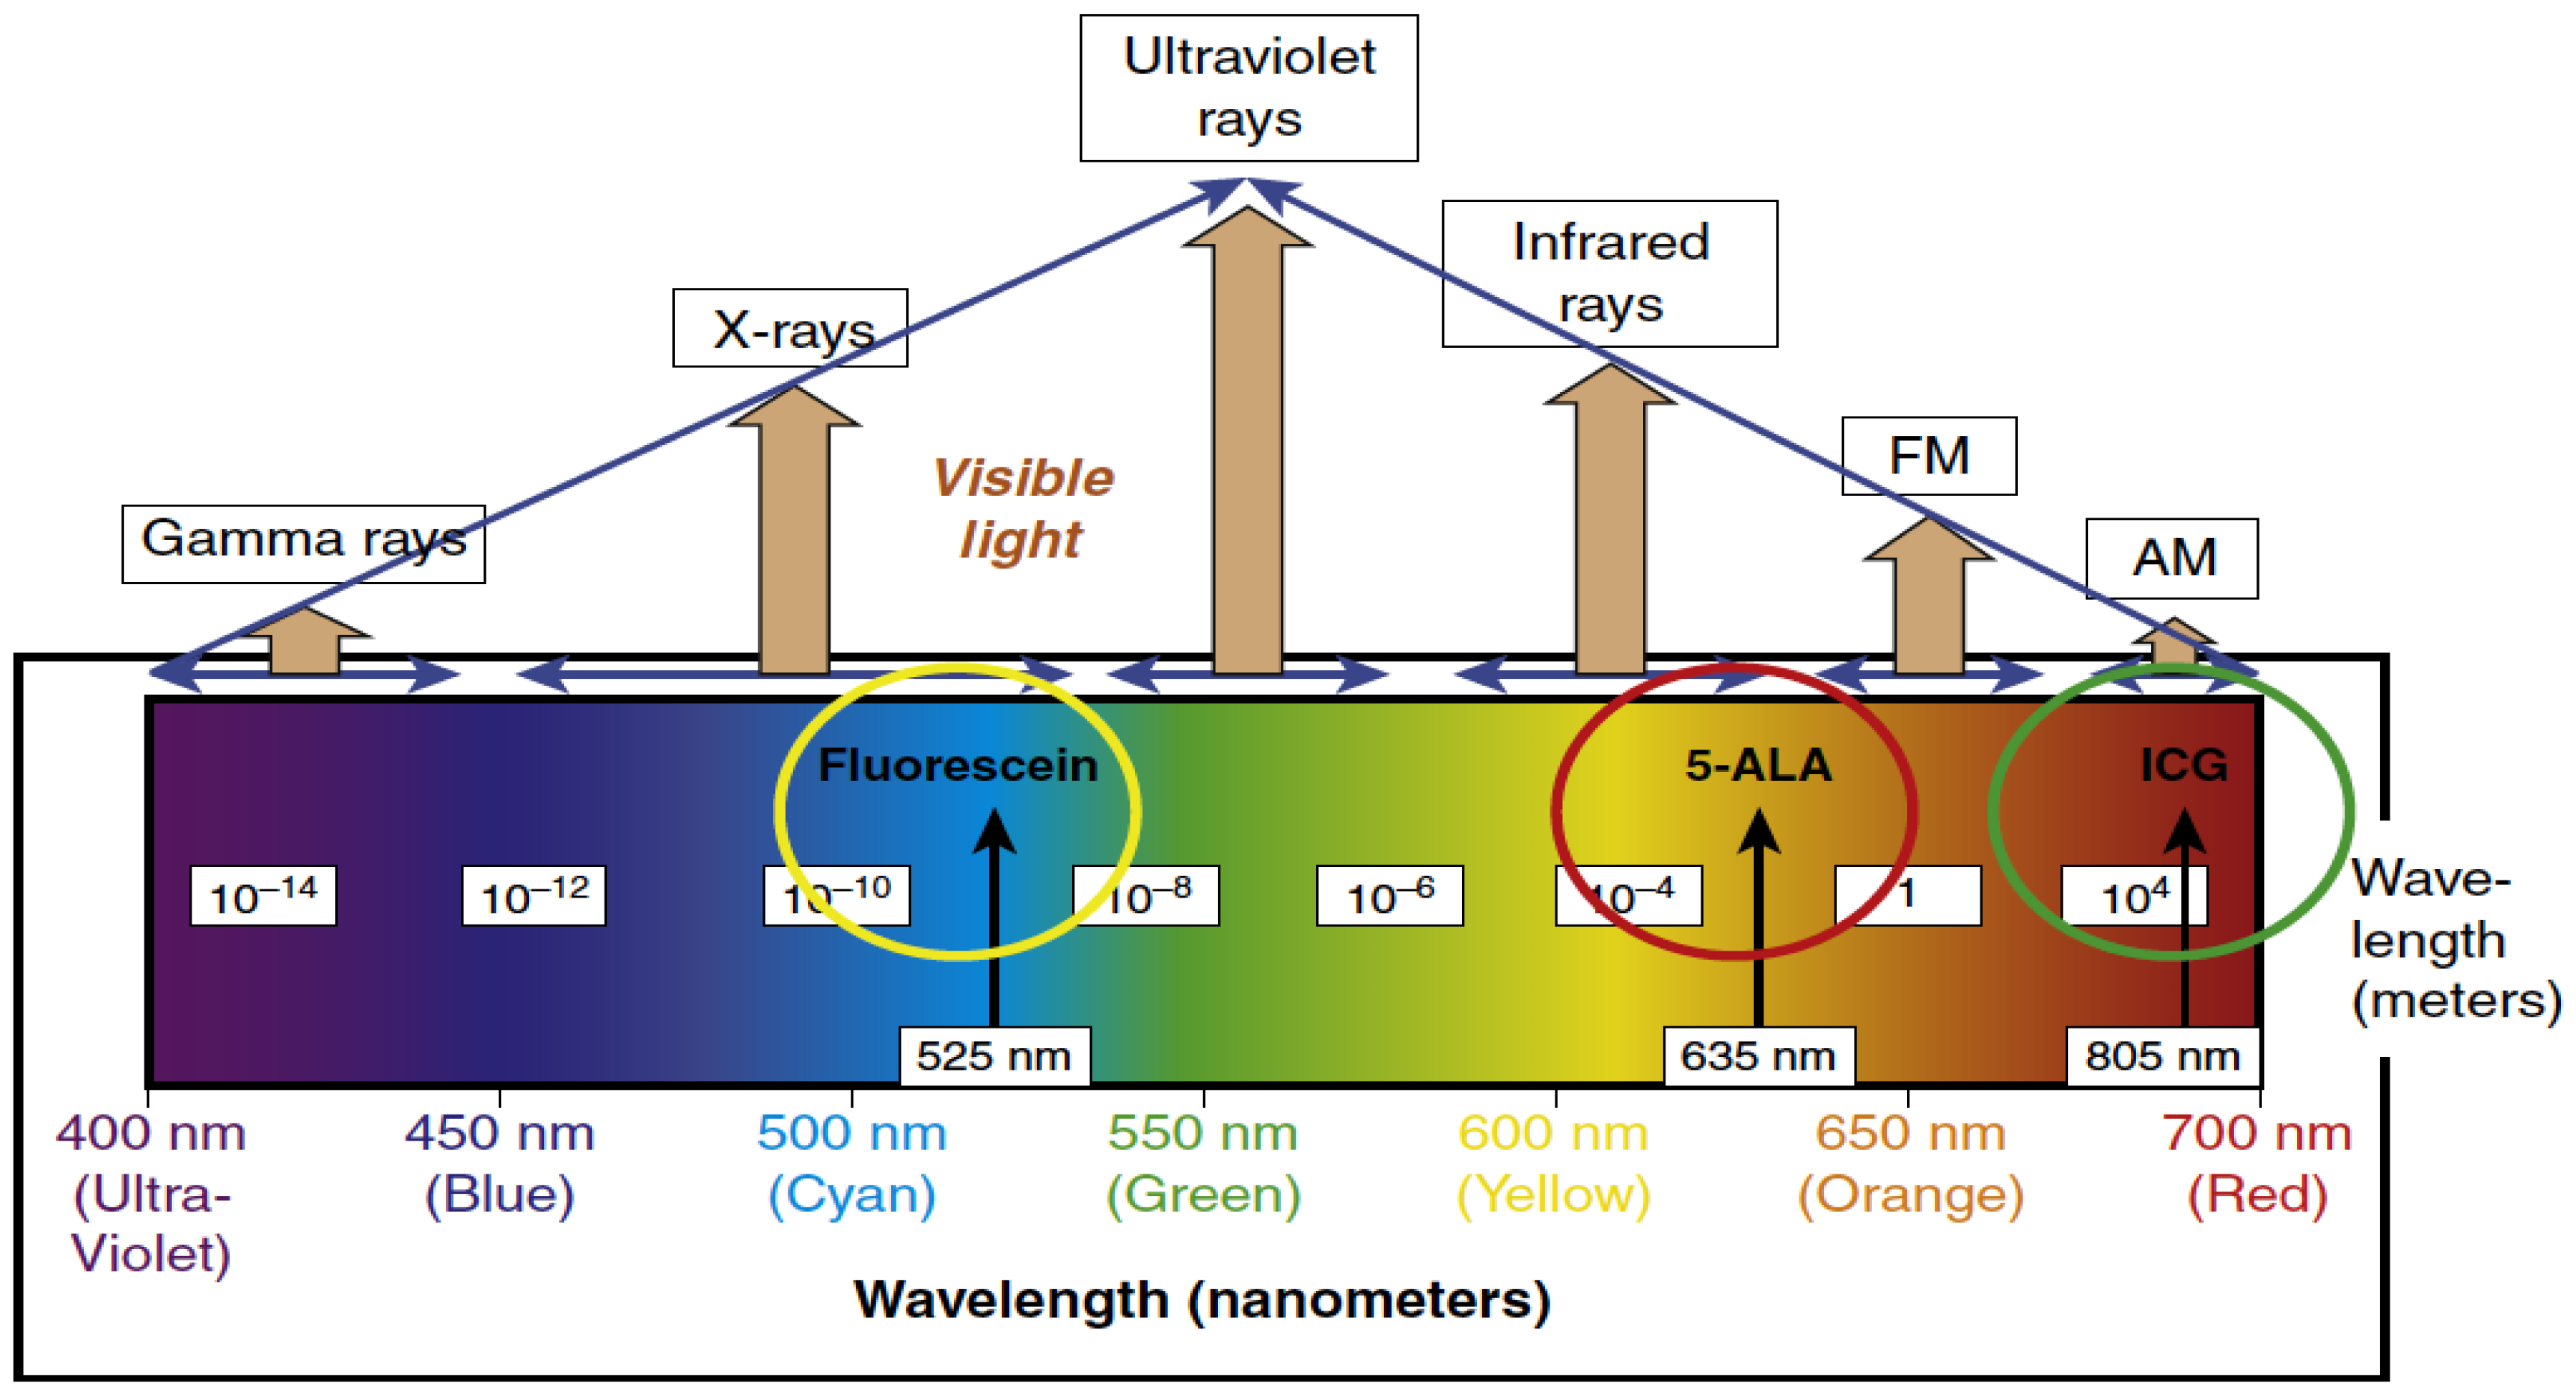

2. Fluorescence-Guided Surgery (FGS)

2.1. 5-Aminolevulinic Acid (5-ALA)

2.2. Fluorescein

2.3. ICG